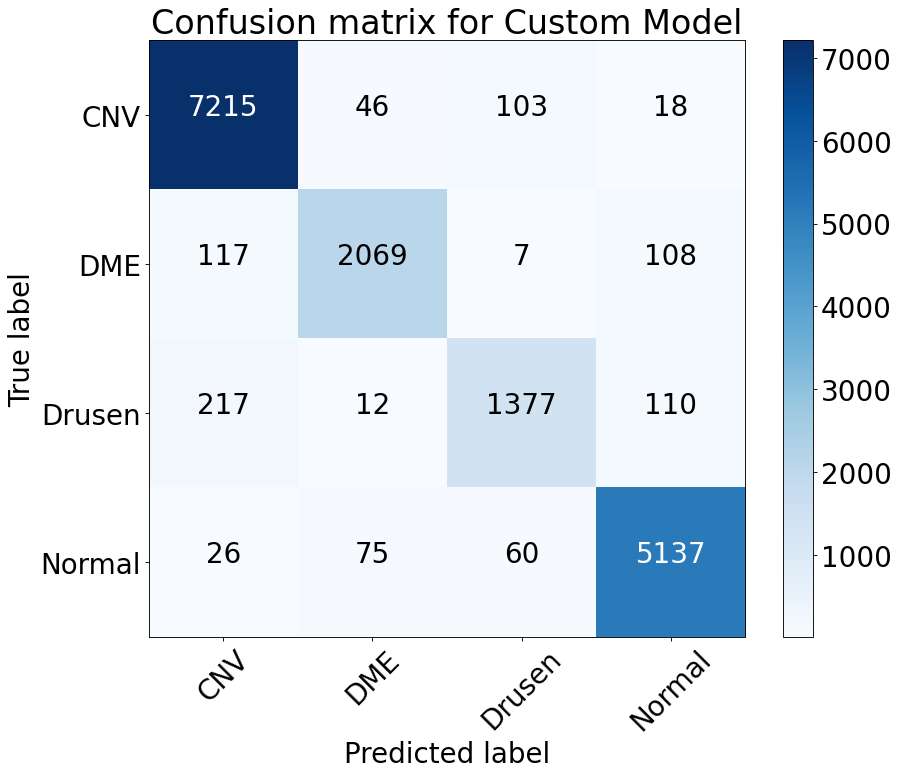

Firstly, if we focus on the models, the self-developed custom model has a clear superiority in terms of performance in all the performance metric. VGG-19 achieves an accuracy of 92.77% on the overall dataset, whereas the custom model reaches 94.87% exceeding that of VGG-19. Not only accuracy but also in terms of other metrics, the custom model always gains a higher value than the VGG-19 model in any of the classes. The precision, F-1 Score, sensitivity values of 0.921, 0.928 and 0.921 respectively of the CNV class from the custom model compared to the 0.898, 0.917 and 0.898 values from VGG-19 model can be given as an example that infers the previous statement. Fig 5 illustrates the confusion matrix of all the labels which is produced from the result of the proposed model

Secondly, another important observation from Table V is among the four classes CNV and Normal class has been comparatively superior in case of all the metrics, as the precision, F1-score and recall of CNV from the custom model are 0.967, 0.966 and 0.967 respectively and that values for the Normal cases are 0.977, 0.964 and 0.977 and similar scenario for the pre-trained model. The reason behind their better performance is the presence of their larger number of data and as the larger, the number of the data, the better the performance of any CNN model would be. The latter statement is also proven by the fact that the Drusen class has provided the poorest result and the quantity of data for this class is also the smallest So, in the end, it can be inferred that the performance of the self-developed custom model, as well as the pre-trained model, can easily be upgraded by collecting more data.